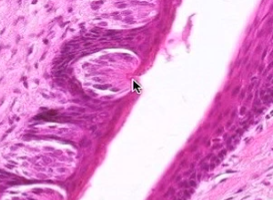

List 3 cell types found within the structure at the arrow.

Sensory cell

Supporting cell

Basal cell

(Taste bud)

The arrow is pointing to which structure? Function?

Taste pore - allows food to get down to taste bud

The blue blob points to cells whose function is to:

Synapse with afferent nerve fibers and transmit taste info

(Elongated cells in taste bud - sensory cells)